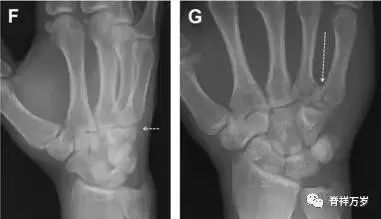

32.掌板骨折

掌板是掌指关节和指间关节关节囊掌侧的纤维结构,防止关节过伸。掌板的远端部是增厚的纤维软骨,附着于指骨掌侧基底部,而其两侧与侧副韧带的纤维融合。掌板骨折多发生于过伸损伤,为撕脱性骨折。

图 3 掌板骨折(A~C)小指前后位、斜位、侧位片,由于骨折的部位及特点,在前后位片上通常难以发现骨折;放大后的斜位(D)、侧位(E)可见一骨碎片(白色箭头)。